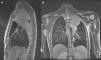

We describe an unusual case (due to the age and lack of any history) of a 17-year-old patient that began with a persistent non-productive cough but no other symptoms, and which did not improve despite antibiotic and analgesic treatment. Laboratory tests revealed hypochromic microcytic anaemia, thrombocytosis and high C-reactive protein (CRP). On the X-ray, a multilobular mass was identified that the chest computed tomography (CT) scan described as a 9cm heterogeneous solid mass in the left upper lobe. Atelectasia of the surrounding lung parenchyma was noted on magnetic resonance imaging (MRI), defining the mass as extrapulmonary and derived from the pleura; it also infiltrated the mediastinum, partially surrounding the left subclavian artery at its origin (Fig. 1). There were no endobronchial changes and bronchial aspirate (BAS) cultures were negative. The study was completed with a positron emission tomography (PET) scan, which showed hypermetabolism of the mass with maximum SUV of 8.55, and no uptake in the mediastinum.